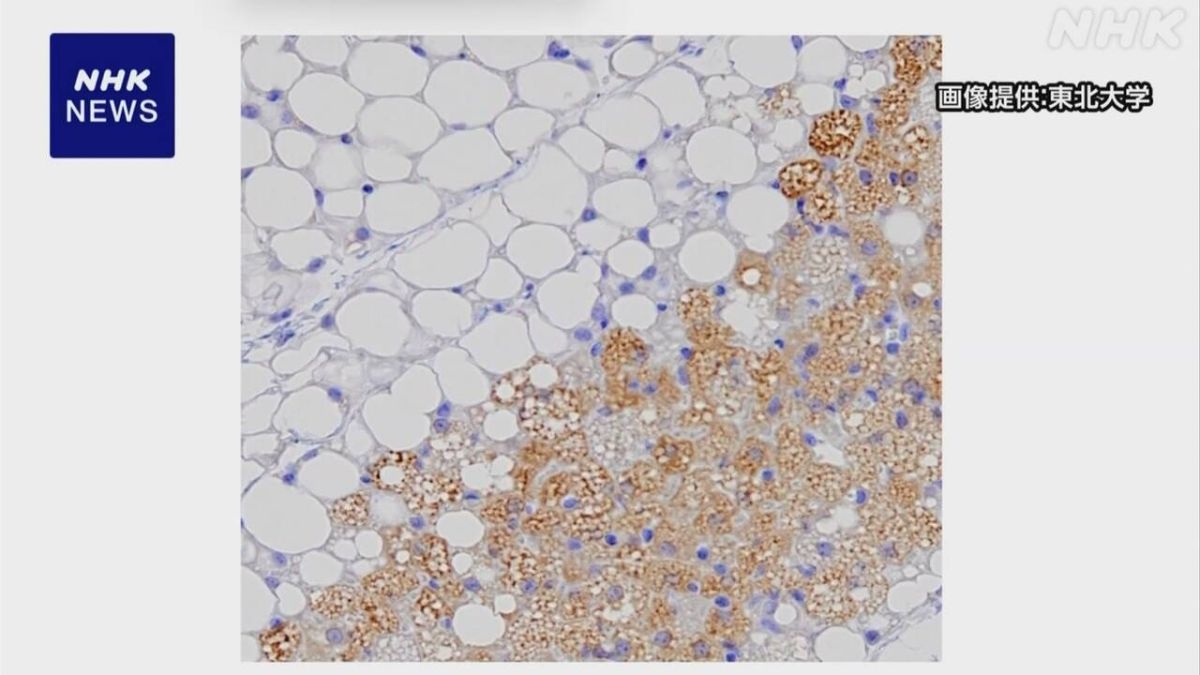

気温が低い時期に受精して生まれた人は体内でエネルギーを消費する「褐色脂肪」の働きが活発で、肥満のリスクが低い傾向があるとする研究結果を東北大学などのグループが発表しました。

ヒトの肩や首の周りにある褐色脂肪という組織は寒い環境でエネルギーを消費して熱を生み出す働きがあり、働きが活発なほど肥満のリスクが低下することが知られています。

東北大学の米代武司准教授らの研究グループは、18歳から29歳の男性およそ360人を対象に、生まれた日から推定した受精の時期の気温と褐色脂肪の活性の関連を調べました。

その結果、10月下旬から4月上旬の気温が低い時期に受精したグループは4月下旬から10月上旬の気温が高い時期に受精したグループより褐色脂肪の活性が平均でおよそ1.3倍高いことがわかりました。

さらに、別の方法で20歳から78歳の男女およそ290人を対象に行った調査でも同じ傾向がみられたほか、内臓脂肪の量もおよそ18%少ないなど、肥満のリスクが低下する可能性が示されたとしています。

マウスでは低い気温にさらされたオスの精子から生まれた子どものマウスで褐色脂肪の活性が高くなることがわかっていましたが、研究グループによりますとヒトで受精した時期の気温と褐色脂肪の活性の関連が明らかになるのは初めてだということです。